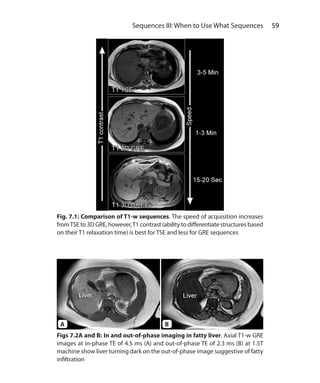

Chapter 7.  Sequences III: When to Use What Sequences	58

T1- Weighted Sequences	 58